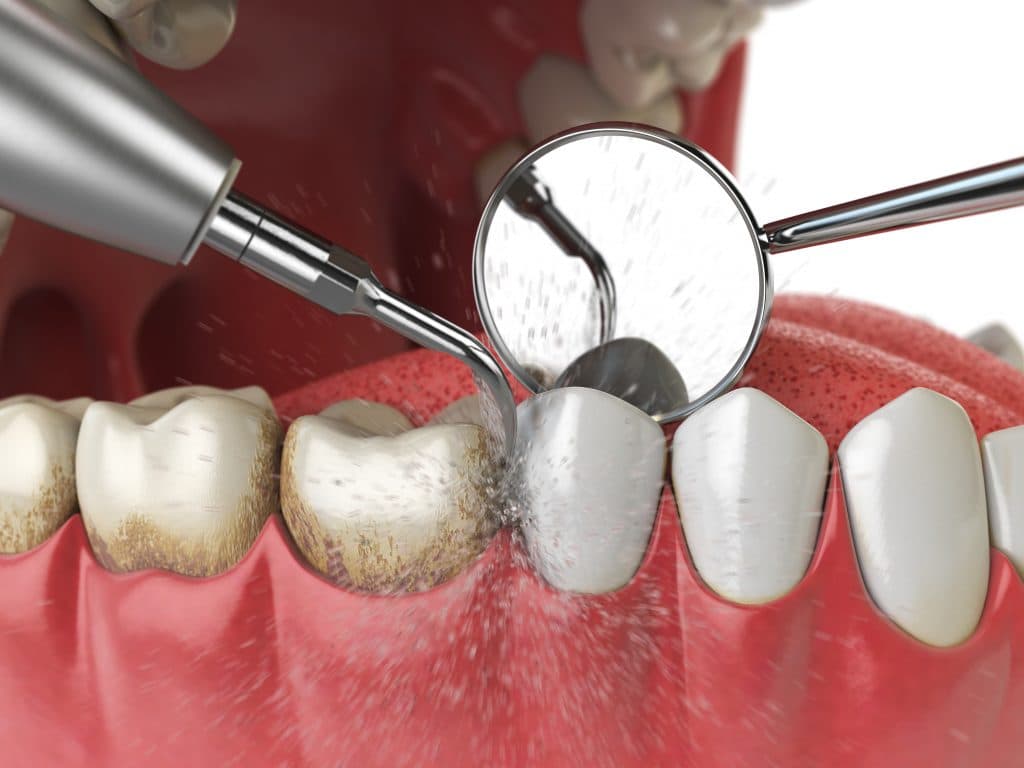

The first therapeutic step is non‑surgical mechanical therapy—professional scaling and root planing (deep cleaning) to remove plaque and calculus from supra‑ and subgingival surfaces and to smooth root surfaces so the gingiva can reattach; adjunctive measures may include local antimicrobial delivery or short courses of systemic antibiotics for selected cases with persistent infection or aggressive presentation.